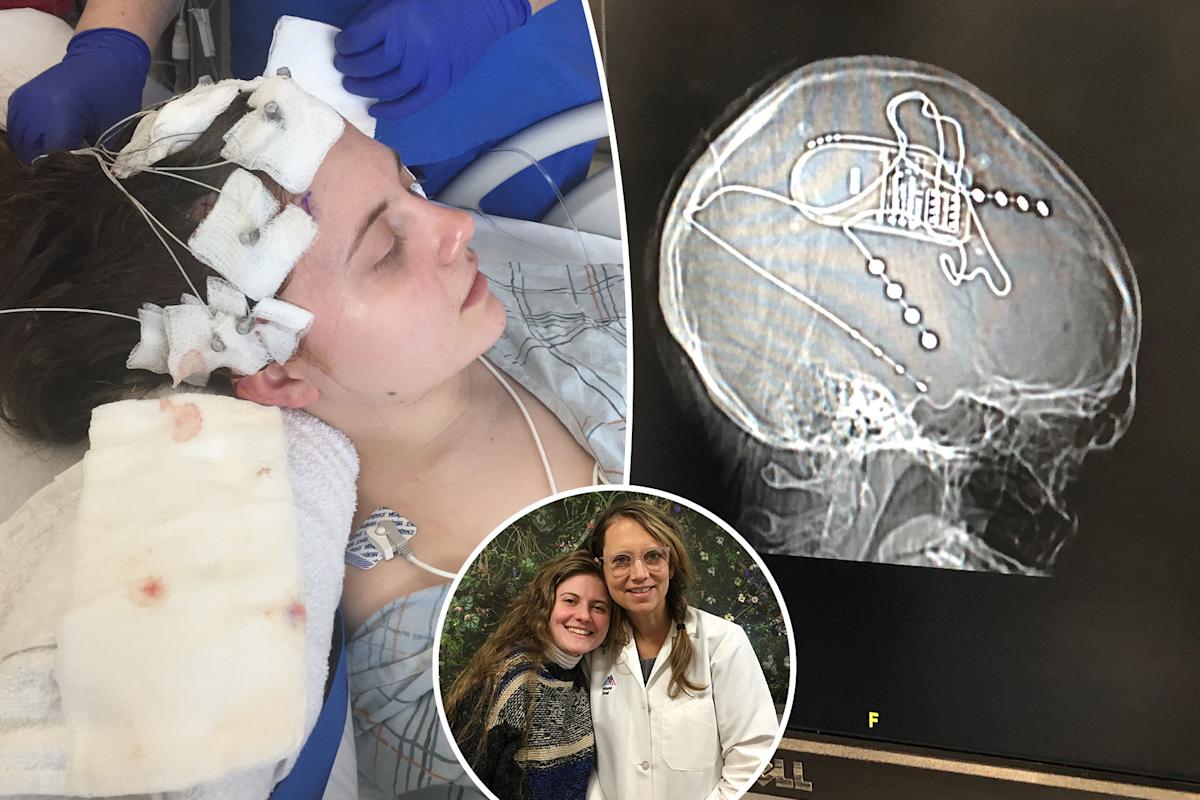

Arielle Hoffman was just 22 years old when she began experiencing strange episodes that altered her consciousness. Courtesy of Arielle Hoffman

Courtesy of Arielle Hoffman

Hoffman and her neurologist, Dr. Lara Marcuse. Courtesy of Arielle Hoffman

Hoffman underwent stereoelectroencephalography to pinpoint where her seizures were starting in the brain. Courtesy of Arielle Hoffman